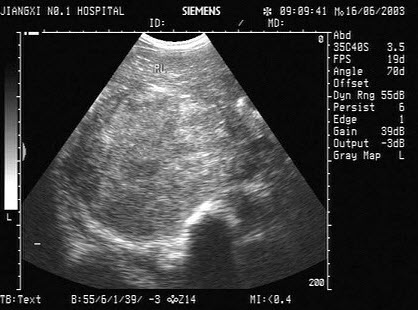

根据以下肝超声检查声像图,诊断为()

A.肝癌并门脉癌栓

B.肝硬化

C.脂肪肝

D.肝炎

E.血吸虫性肝硬化并门脉血栓